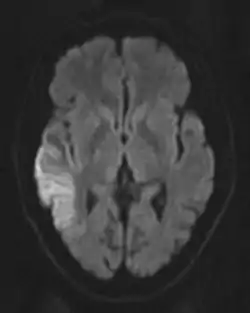

رایجترین کاربرد DW-MRI در تصویربرداری از مغز بلافاصله پس از انفارکسیون است، یا بهطور دقیقتر پس از حالت ایسکمی که در آن بافتهای شرکت کننده، آبهای جذب شده از فضای خارج سلولی را از دست بدهند. این مدت معمولاً چند روز پس از واقعه ایسکمی بتدریج رخ میدهد. در این مدت، خاصیت پخشی بافتها حالتی محدود داشته، و ADC بافتها کاهش مییابد. در نتیجه بافت صدمه دیده دارای شدت سیگنال بیشتری میشود (تصویر مقابل)، و میتوان از این خاصیت برای تمیز دادن از بافتهای سالم استفاده کرد.